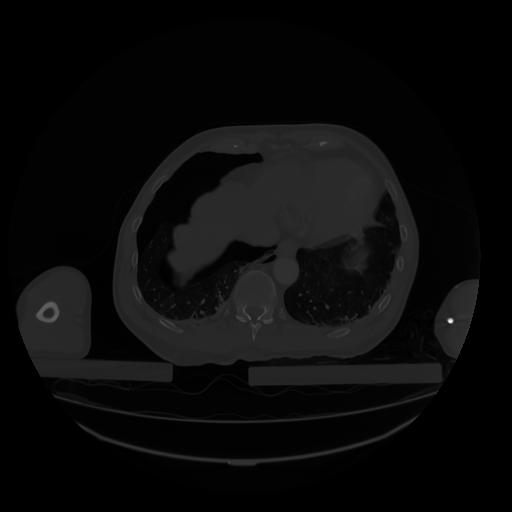

28 CUERPO,CE,Vol,2.0,CUERPO,,